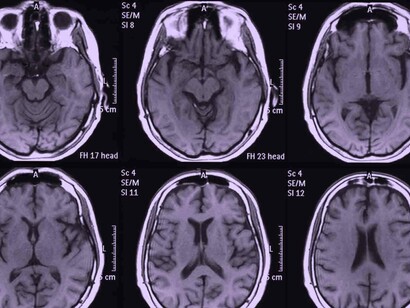

Se está observando la presencia de ictus o accidentes cerebrovasculares (ACV) en adultos jóvenes (menores de 50 años) sin factores de riesgo cardiovascular que sufren COVID-19. Es decir, personas sin la edad ni los factores de riesgo suficientes como para esperar un ictus. Se especula si realmente hay un aumento significativo, pues aún se han descrito pocos casos, o si realmente la infección favorece el desarrollo de estos.

En un artículo publicado en The Lancet del pasado mes de abril, se trata el tema de por qué los accidentes cerebrovasculares están ocurriendo en jóvenes aparentemente sanos. En dicho artículo, investigadores del Hospital Universitario de Zúrich notaron que el virus SARS-CoV-2 (COVID-19) infecta a los huéspedes a través de la enzima convertidora de angiotensina (ACE2), expresado no solo en los pulmones sino también en el corazón, riñón, intestino y células endoteliales. Y describieron tres casos en los que observaron infección viral directa de las células e inflamación endotelial difusa (endotelitis). La endotelitis por COVID-19 podría explicar la función microcirculatoria deteriorada en diferentes lechos vasculares y sus secuelas clínicas en pacientes con COVID-19.

Investigadores holandeses describieron otro posible mecanismo detrás del aparente aumento del riesgo de accidente cerebrovascular en un artículo publicado en línea, en abril, en la revista Thrombosis Research. En 184 pacientes de la UCI con neumonía comprobada por COVID-19, se observó un resultado de embolia pulmonar aguda sintomática, trombosis venosa profunda, accidente cerebrovascular isquémico, infarto de miocardio o embolia arterial sistémica en un 31%, una cifra que llamaron «notablemente» alta. Se especula un problema con el sistema de coagulación o con el revestimiento endotelial de los vasos sanguíneos.

Cualquiera que sea la causa del mayor riesgo de accidente cerebrovascular asociado con COVID-19, se ha visto que, tanto la presentación como el resultado, son a menudo peores que en otros accidentes cerebrovasculares. Por lo general, estos pacientes con COVID-19 presentan más de un vaso bloqueado con un trombo. En el estudio de una serie de casos, la mortalidad fue de alrededor del 55 por ciento. A pesar de reabrir los vasos obstruidos, terminan teniendo otro ictus importante. Su sangre sigue coagulándose con rapidez.